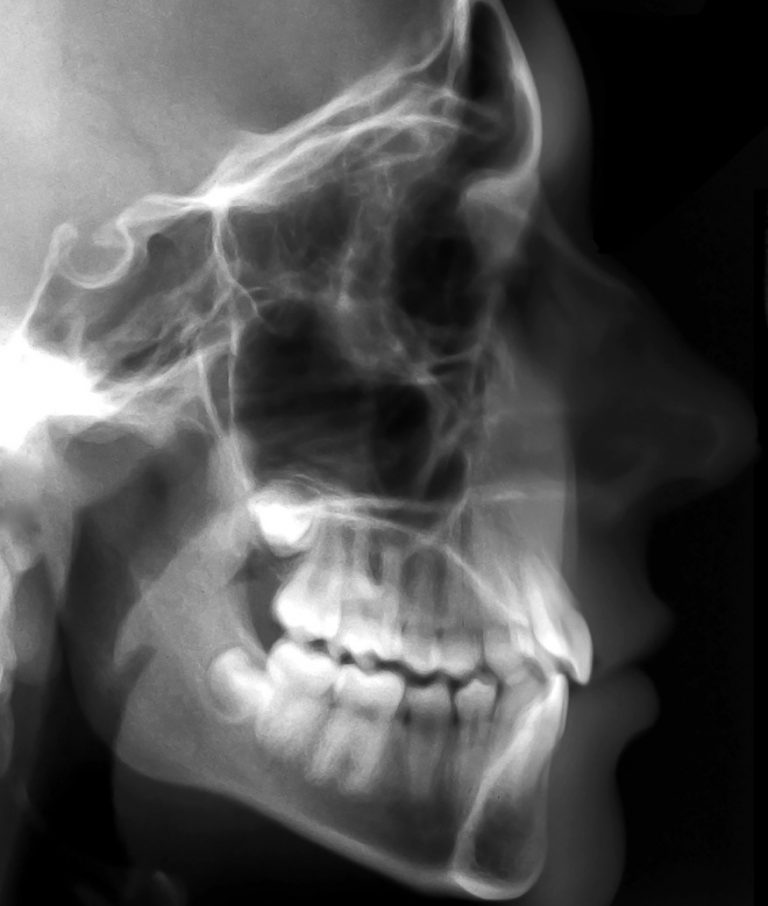

Fernröntgenseitenaufnahme (FRS):

Dieses Röntgenprofilbild gehört neben der

klinischen Befunderhebung, der Modellanalyse und dem OPT zu den wichtig

sten Behandlungsunterlagen. Es erfolgt eine Auswertung und detaillierte Vermessung. Der Informationsinhalt umfasst: Stellung der Frontzähne, das Knochenangebot im Frontzahnbereich, die Kieferlage (Rück- oder Vorlage), das Wachstumsmuster (skelettal offener oder tiefer Biss), die Form des Unterkiefers, Weichteilverlauf, Lippenlage und Lippenvolumen. Insbesondere bei sehr großen Frontzahnstufen kann man anhand dieser Aufnahme dentale Befunde (Zahnstellung der Frontzähne) und skelettale Befunde (Kieferlage) gegeneinander abgrenzen.

Fernröntgenseitenaufnahme (FRS)